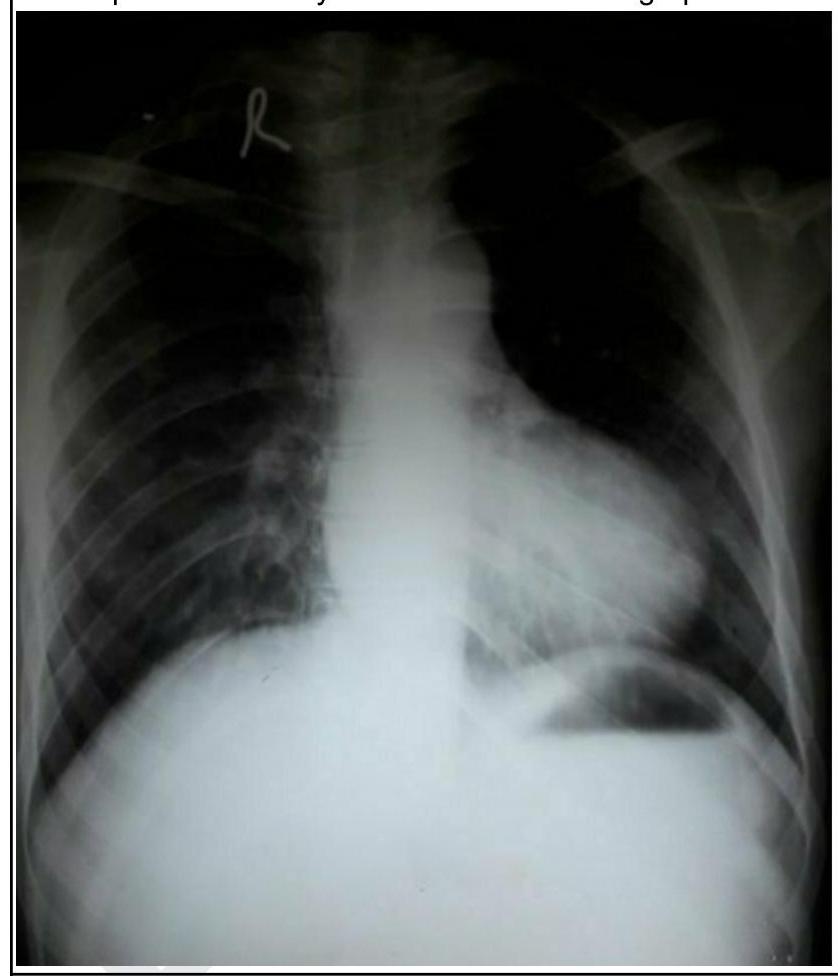

A child presents with cyanosis. His chest radiograph is shown below. What is the diagnosis?

Explanation: ***Tetralogy of Fallot (TOF)*** - The chest radiograph shows a **boot-shaped heart (coeur en sabot)** due to **right ventricular hypertrophy** and a **concave pulmonary artery segment** (absent main pulmonary artery segment), which is characteristic of TOF. - The patient also presents with **cyanosis**, a common symptom of TOF due to right-to-left shunting. *Transposition of great arteries (TGA)* - TGA typically presents with a **"egg-on-a-string" appearance** on chest radiograph, indicating a narrow superior mediastinum and increased pulmonary vascular markings, which is not seen here. - While patients with TGA are cyanotic, the cardiac silhouette on this radiograph is inconsistent with the classic TGA findings. *Ebstein's anomaly* - Ebstein's anomaly is characterized by **apical displacement of the tricuspid valve**, leading to a large right atrium and massive **cardiomegaly** on chest X-ray, often described as a "box-shaped" heart, which is not evident in the provided image. - While it causes cyanosis, the heart size in the image is not markedly enlarged enough to suggest Ebstein's anomaly. *Total anomalous pulmonary venous return (TAPVC)* - TAPVC typically presents with a **"snowman" or "figure-of-8" appearance** on chest X-ray due to a dilated superior vena cava and left brachiocephalic vein, or a small heart with increased pulmonary vascularity, neither of which is present in the image. - Although TAPVC causes cyanosis, the specific radiographic features like the "boot-shaped" heart rule out this diagnosis.